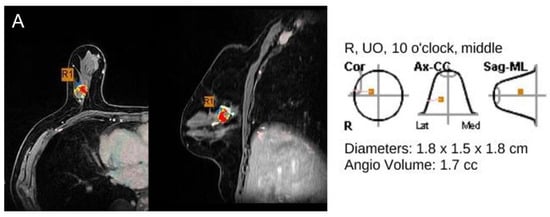

Figure 3.

78-year-old woman with invasive ductal carcinoma in right breast. (A,B) Maximal diameter by CAD, radiologist and pathology were 1.8 cm, 2.1 cm, and 1.8 cm. Both CAD-and radiologist-measured sizes were accurate, in reference to pathology. This cancer was of luminal B subtype, negative EIC at pathology and mass type on MRI (R: right, UO: upper outer).